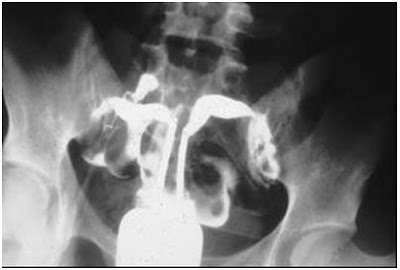

Fig. 10 - Útero

didelfo. Histerosalpingografía en donde se observan dos cavidades uterinas con

marcada impronta en fondo uterino. (8)